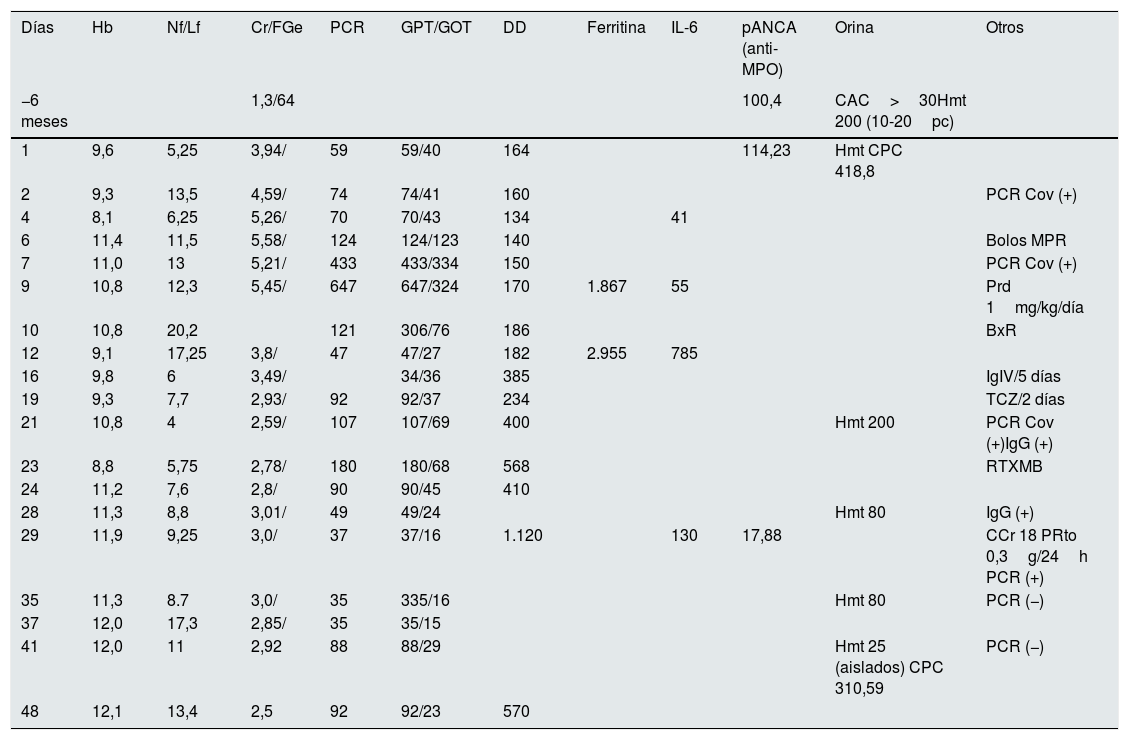

Evolución analítica

| Días | Hb | Nf/Lf | Cr/FGe | PCR | GPT/GOT | DD | Ferritina | IL-6 | pANCA (anti-MPO) | Orina | Otros |

|---|---|---|---|---|---|---|---|---|---|---|---|

| −6 meses | 1,3/64 | 100,4 | CAC>30Hmt 200 (10-20pc) | ||||||||

| 1 | 9,6 | 5,25 | 3,94/ | 59 | 59/40 | 164 | 114,23 | Hmt CPC 418,8 | |||

| 2 | 9,3 | 13,5 | 4,59/ | 74 | 74/41 | 160 | PCR Cov (+) | ||||

| 4 | 8,1 | 6,25 | 5,26/ | 70 | 70/43 | 134 | 41 | ||||

| 6 | 11,4 | 11,5 | 5,58/ | 124 | 124/123 | 140 | Bolos MPR | ||||

| 7 | 11,0 | 13 | 5,21/ | 433 | 433/334 | 150 | PCR Cov (+) | ||||

| 9 | 10,8 | 12,3 | 5,45/ | 647 | 647/324 | 170 | 1.867 | 55 | Prd 1mg/kg/día | ||

| 10 | 10,8 | 20,2 | 121 | 306/76 | 186 | BxR | |||||

| 12 | 9,1 | 17,25 | 3,8/ | 47 | 47/27 | 182 | 2.955 | 785 | |||

| 16 | 9,8 | 6 | 3,49/ | 34/36 | 385 | IgIV/5 días | |||||

| 19 | 9,3 | 7,7 | 2,93/ | 92 | 92/37 | 234 | TCZ/2 días | ||||

| 21 | 10,8 | 4 | 2,59/ | 107 | 107/69 | 400 | Hmt 200 | PCR Cov (+)IgG (+) | |||

| 23 | 8,8 | 5,75 | 2,78/ | 180 | 180/68 | 568 | RTXMB | ||||

| 24 | 11,2 | 7,6 | 2,8/ | 90 | 90/45 | 410 | |||||

| 28 | 11,3 | 8,8 | 3,01/ | 49 | 49/24 | Hmt 80 | IgG (+) | ||||

| 29 | 11,9 | 9,25 | 3,0/ | 37 | 37/16 | 1.120 | 130 | 17,88 | CCr 18 PRto 0,3g/24h PCR (+) | ||

| 35 | 11,3 | 8.7 | 3,0/ | 35 | 335/16 | Hmt 80 | PCR (−) | ||||

| 37 | 12,0 | 17,3 | 2,85/ | 35 | 35/15 | ||||||

| 41 | 12,0 | 11 | 2,92 | 88 | 88/29 | Hmt 25 (aislados) CPC 310,59 | PCR (−) | ||||

| 48 | 12,1 | 13,4 | 2,5 | 92 | 92/23 | 570 |

CAC: cociente albúmina/creatinina; CCr: aclaramiento de creatinina en ml/min; CPC: cociente proteína creatinina en mg/ Cr; Cr/FGe: creatinina en sangre en mg/dl y filtrado glomerular estimado CDK-EPI; DD: dímero D (turbidimétrico) en μg/l; Ferritina en ng/ml; GPT/GOT: transaminasas en U/l; Hb: hemoglobina en g/dl; HMT: hematíes en orina elemental; IgG: inmunoglobulina G frente al SARS-CoV-2; IgIV: inmunoglobulinas intravenosas; IL-6: interleucina 6 en pgr/mL; MPR: metilprednisolona a dosis de 250mg/d/3 días; Nf/Lf: ratio neutrófilos/linfocitos; pANCA: anticuerpos anticitoplasma, patrón mieloperoxidasa (MPO) en U/l; PCR: proteína C reactiva en mg/l; PCR CoV: RT-PCR frente al SARS-CoV-2; PRTo: proteinuria en orina de 24h en g/día; RTX: rituximab; TCZ: tocilizumab.